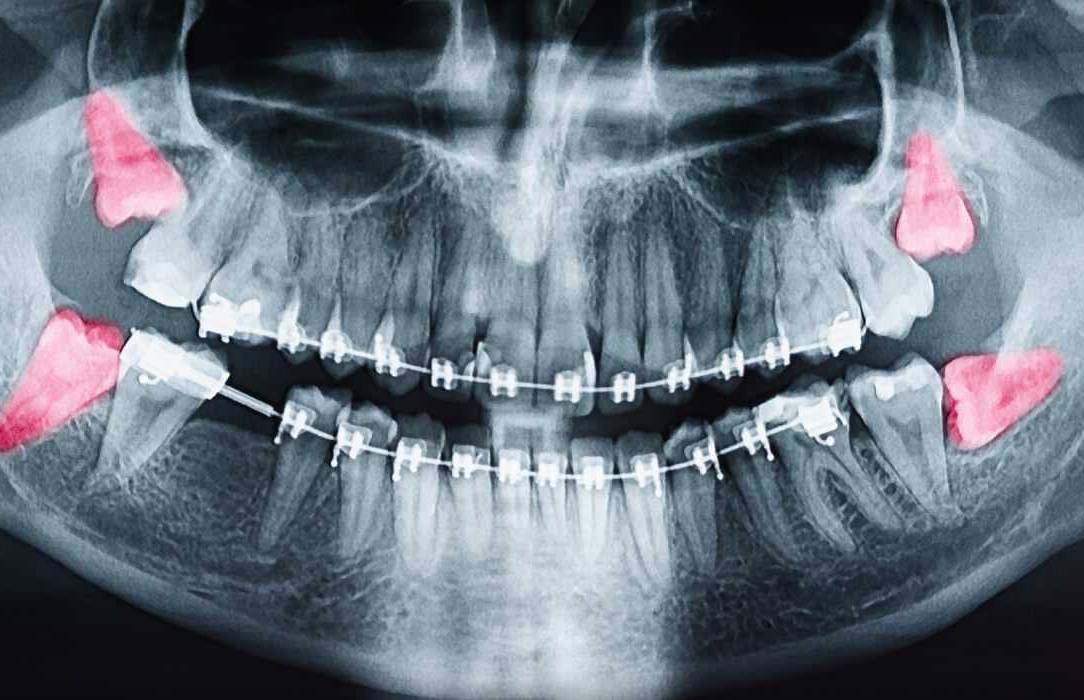

Tooth Extractions

Wisdom tooth extractions are a fairly common procedure. Wisdom teeth often cause problems as they are trying to protrude through the gums. When a wisdom tooth is impacted, it means the tooth is coming in at an angle and not straight through the gum line.